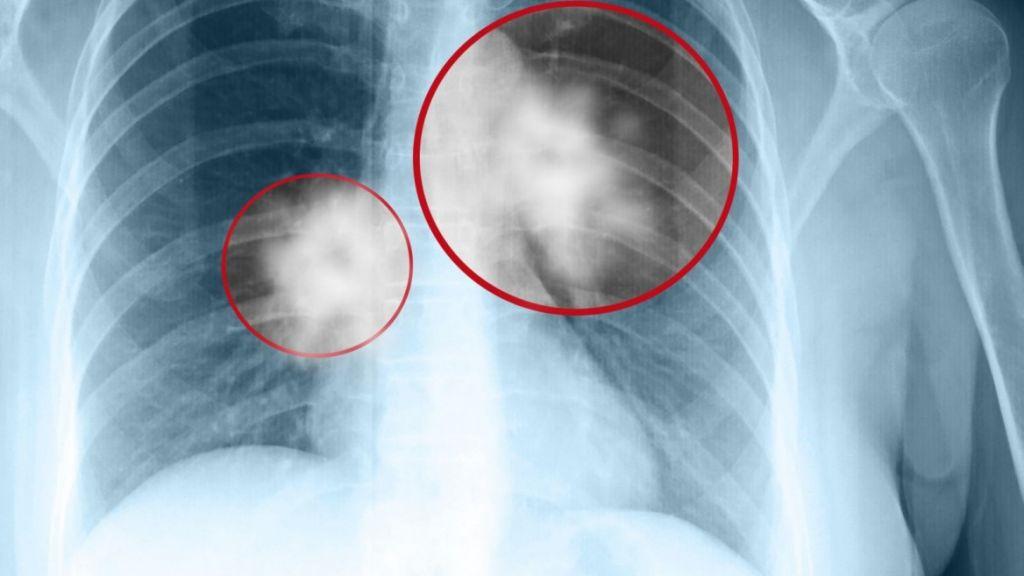

Θεραπεία βελτιώνει την επιβίωση ασθενών με καρκίνο πνεύμονα

Σύμφωνα με νεότερα δεδομένα της μελέτης φάσης ΙΙΙ ALEX ,το alectinib υπερτριπλασίασε τη διάμεση επιβίωση χωρίς εξέλιξη της νόσου σε ασθενείς με νεοδιαγνωσθέντα θετικό στην κινάση αναπλαστικού λεμφώματος (ALK)-προχωρημένο μη μικροκυτταρικό καρκίνο του πνεύμονα (ΜΜΚΠ) σε σχέση με την κριζοτινίμπη, που παρουσιάστηκαν στο πρόσφατο ετήσιο συνέδριο της Αμερικανικής Εταιρείας Κλινικής Ογκολογίας (ASCO).

Πιο συγκεκριμένα, σύμφωνα με τα δεδομένα από τη μελέτη φάσης ΙΙΙ ALEX, το alectinib μείωσε σημαντικά τον κίνδυνο εμφάνισης εξέλιξης της νόσου ή θανάτου (PFS) κατά 57% σε σύγκριση με τη κριζοτινίμπη μετά από δύο έτη παρακολούθησης, στους ασθενείς με νεοδιαγνωσθέντα ALK-θετικό ΜΜΚΠ, ενώ η διάμεση PFS στα άτομα που έλαβαν alectinib υπερτριπλασιάστηκε σε σύγκριση με εκείνους που έλαβαν κριζοτινίμπη, φτάνοντας σχεδόν τα τρία χρόνια (34,8 μήνες) έναντι 10,9 μηνών αντίστοιχα (HR=0,43, 95% CI: 0,32-0,58). Το προφίλ ασφάλειας του alectinib ήταν συνεπές με εκείνο που παρατηρήθηκε σε προηγούμενες μελέτες.

Ο ALK-θετικός ΜΜΚΠ είναι μια διακριτή μορφή καρκίνου του πνεύμονα, που συνήθως προσβάλλει νεότερα άτομα (διάμεση ηλικία 52 έτη) και άτομα με ελαφρύ ιστορικό καπνίσματος ή μη καπνιστές. Περίπου 75.000 άτομα διαγιγνώσκονται με ALK-θετικό ΜΜΚΠ κάθε χρόνο παγκοσμίως. Στην Ελλάδα εκτιμάται πως ο αριθμός αυτός είναι περίπου 80 άτομα.